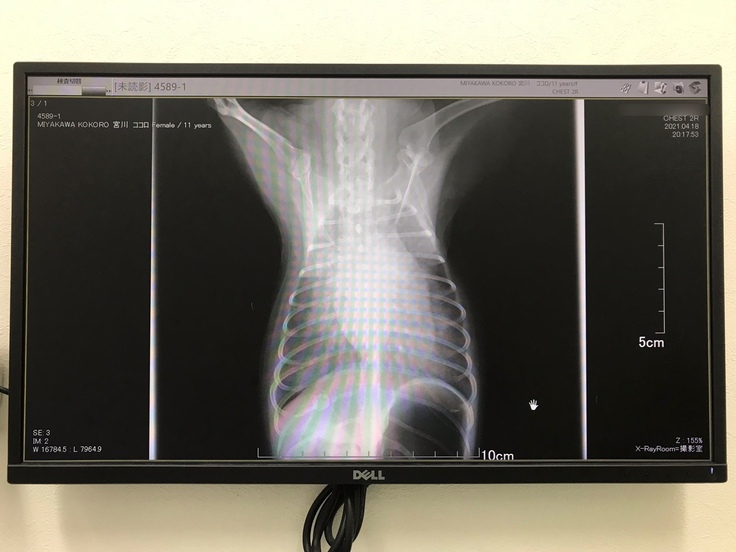

(4月18日のレントゲン写真です。心臓が肥大しており、心臓の周りが白くなっていて肺にお水が溜まってしまっている状態です。)

2021年4月18日(僧帽弁閉鎖不全症の悪化・肺水腫)

主治医の先生からご連絡があり、入院中のこころが肺水腫を起こして、命が危ないかもしれないとの知らせを受けました。てんかん発作で入院していたのに何故そんなことに…と目の前が真っ暗になり、苦しむこころを想うと涙が止まりませんでした。

先生から「今回起こしたてんかん発作が引き金となり、急激に心臓が肥大して僧帽弁閉鎖不全症が悪化し、肺水腫を起こしたため、なるべく早く心臓の手術をしなければ、肺水腫で苦しんで最期のときを迎えるのを待つしかなく、余命幾ばくもない」と宣告され、こころを失うかもしれない恐怖で頭がいっぱいになりました。

3月の定期検診では問題なく、安心していた矢先、突然このようなことになる等、思ってもみなかったことでした。

こころの場合、心臓の大きさが、通常は4年程かけてゆっくりと肥大していく大きさに、わずか1日で悪化したとのことです。 そのため、通常よりも手術を急がねばならず、手術をすれば肺水腫も心臓も良くなる、こころは助かって、寿命を全うできるだろうと言われたときには、手術で何とか助けられるのなら、どうにかして手術を受けさせてあげたい…どうにか苦しい状態から救い出してあげたいと強く思いました。